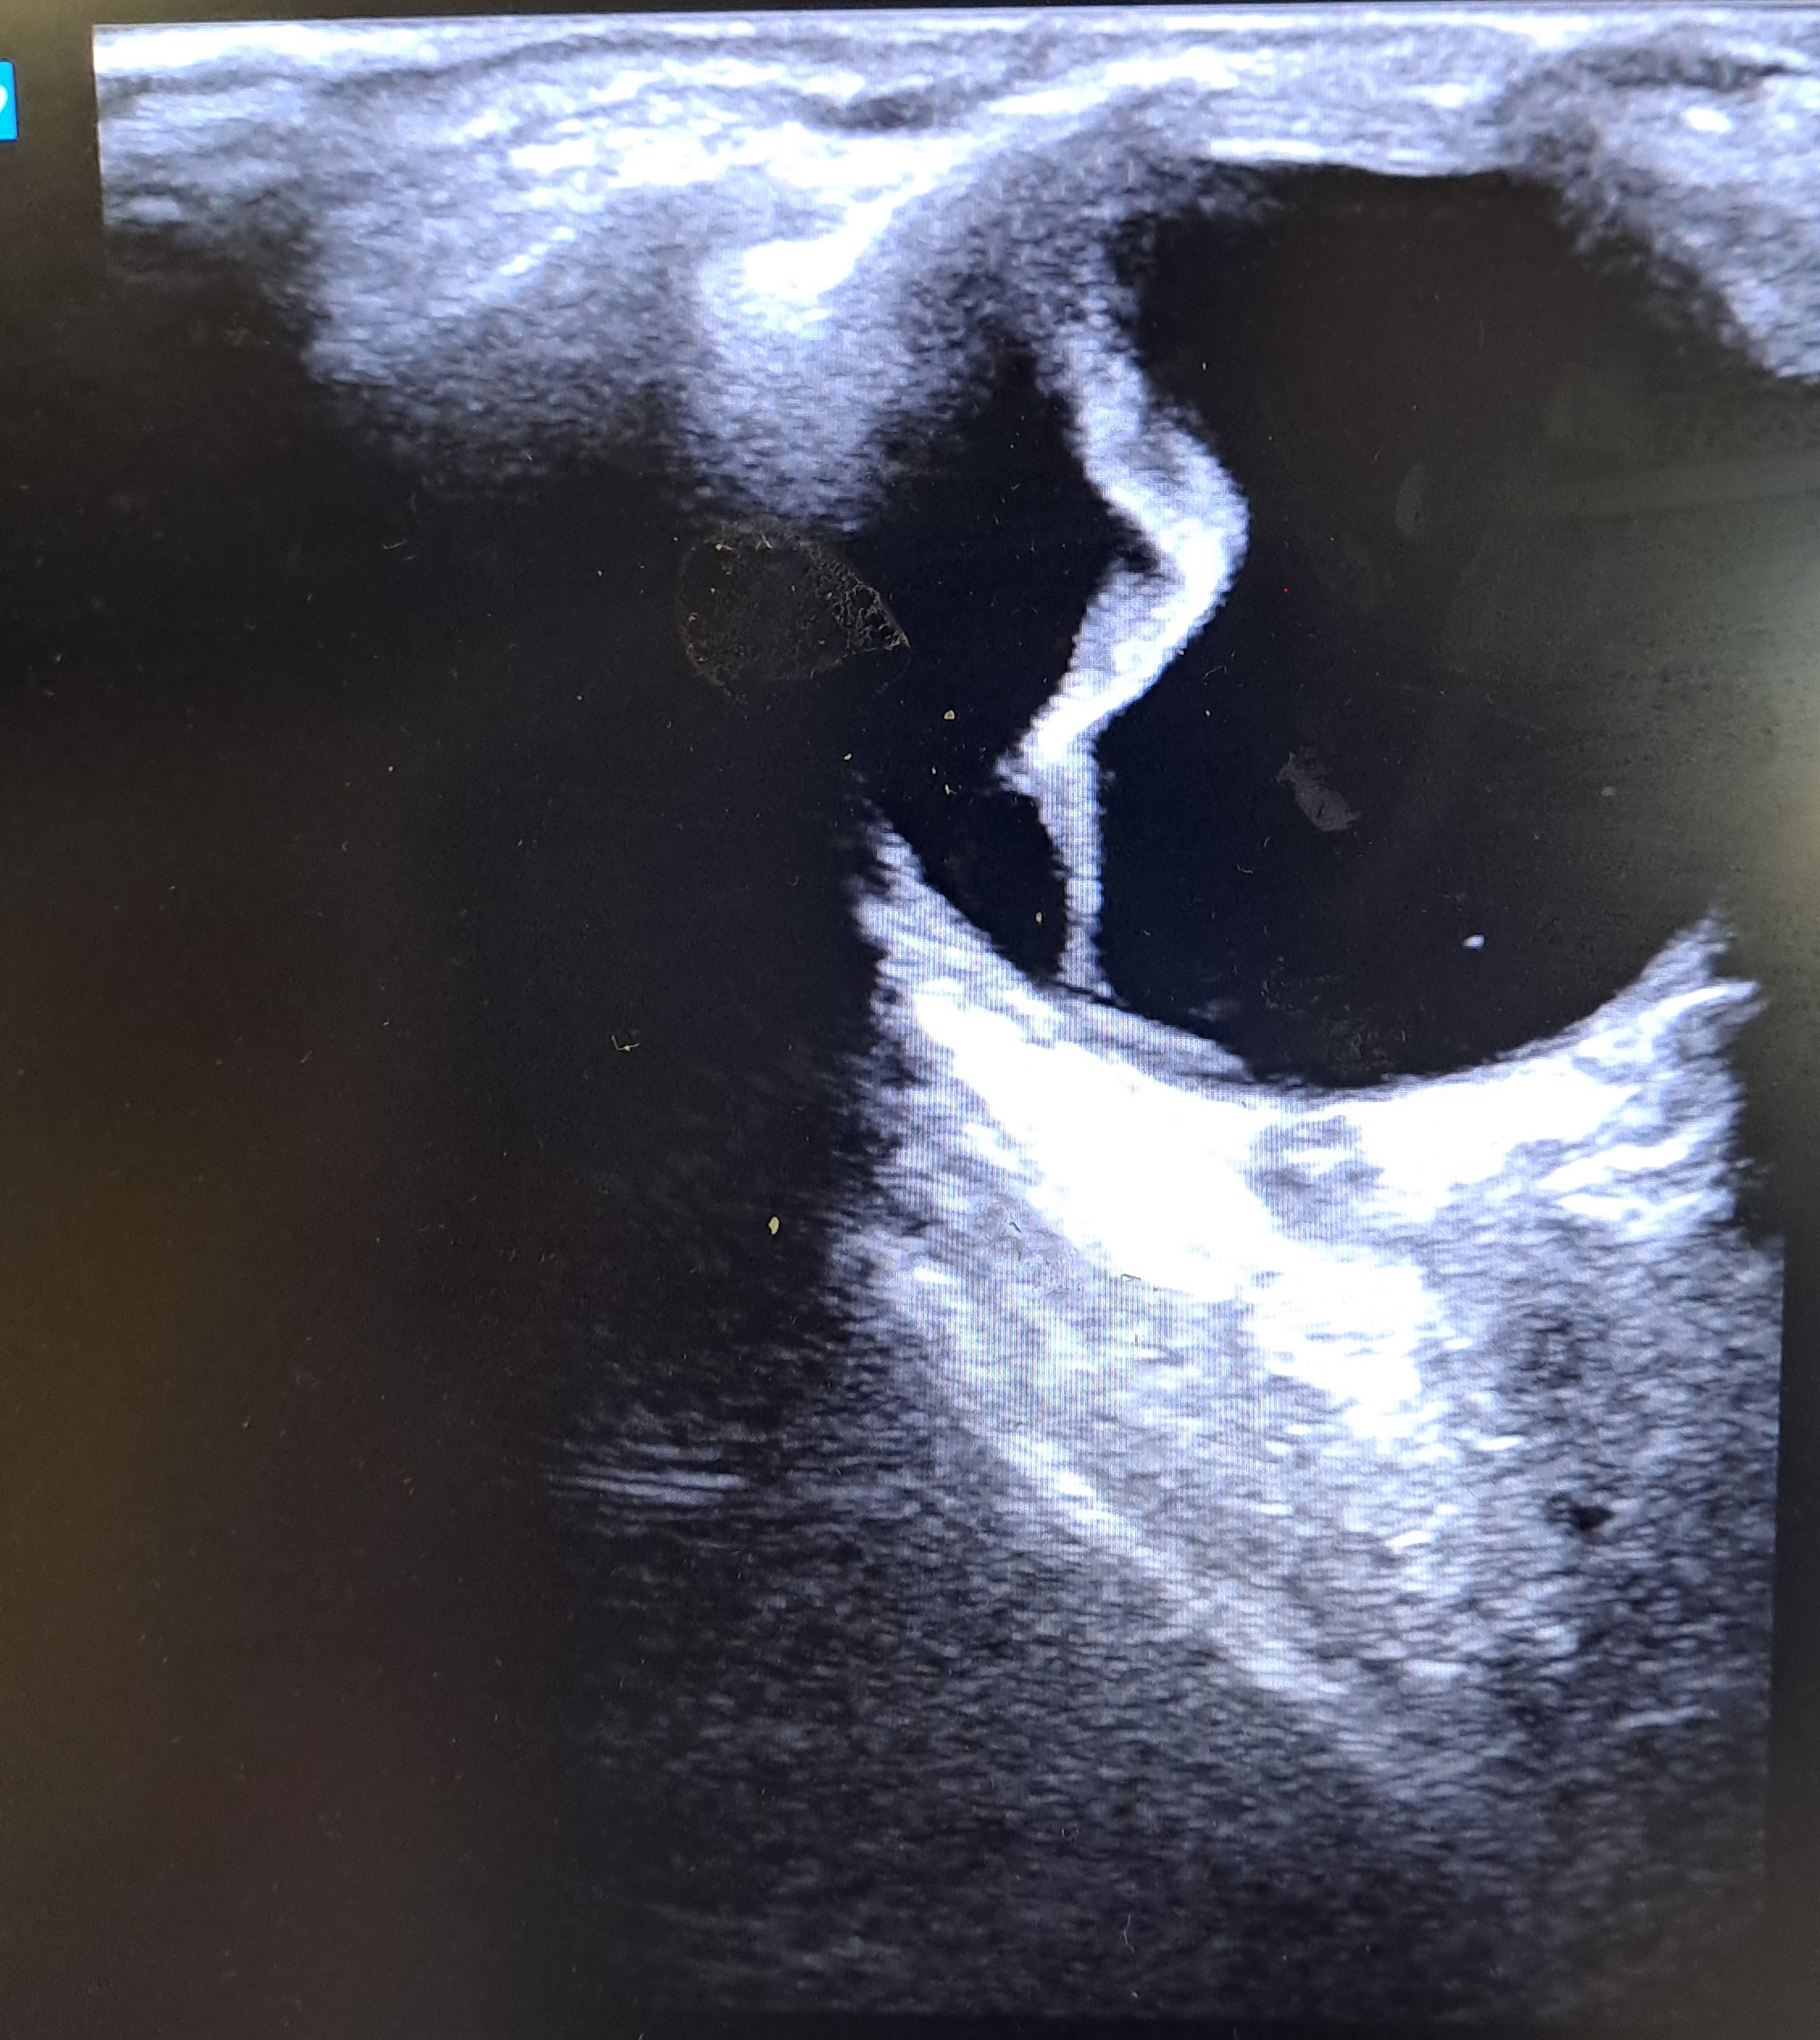

Se realiza ecografía clínica para valoración de ojo derecho.

Se realiza ecografía clínica objetivando línea hiperecogénica en región temporal-central del ojo derecho a la altura del humor vítreo.

Desprendimiento de retina extensa en región temporal en ojo derecho.